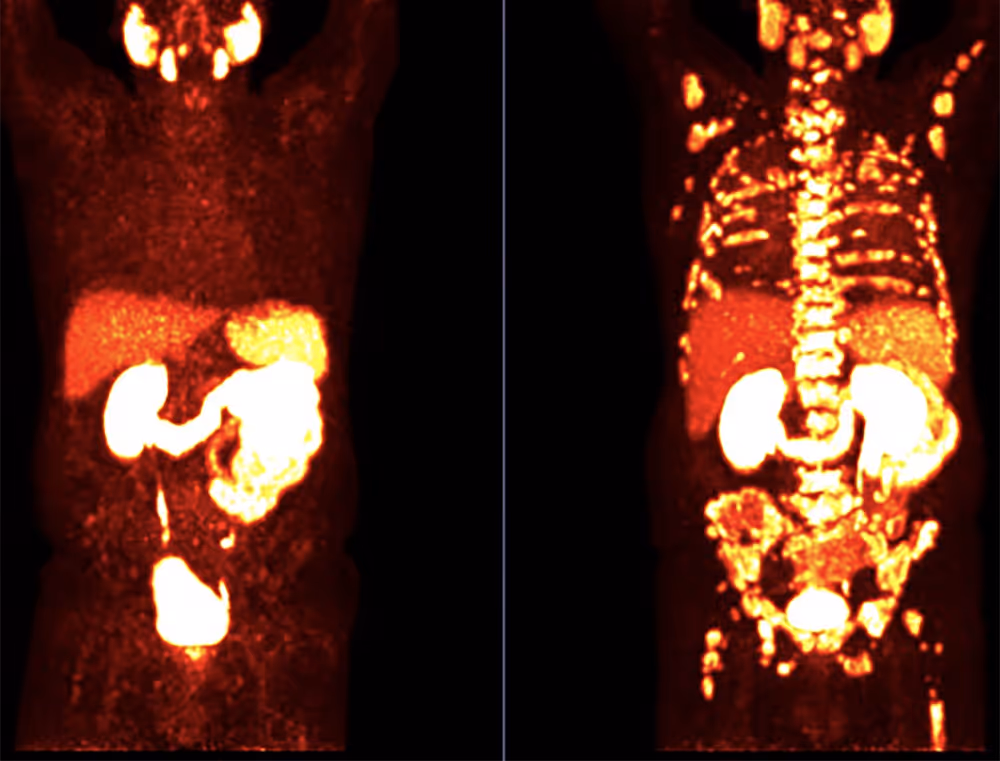

- moderne molekulare Bildgebung wie die PSMA PET/CT, insbesondere bei fortgeschrittenem Stadium oder bei erneut steigendem PSA-Wert

Gerade bei Verdacht auf Metastasen oder bei unklaren Befunden kann die PSMA PET/CT zusätzliche, präzisere Informationen liefern und so die Therapieplanung wesentlich beeinflussen.

Bei fortgeschrittenem oder metastasiertem Prostatakrebs gewinnt zusätzlich die genaue Beurteilung der Tumorlast und -verteilung an Bedeutung. Hier kann eine PSMA PET/CT helfen, selbst kleine Metastasen präzise sichtbar zu machen und die Therapieplanung gezielt auszurichten.

- PSMA PET/CT als moderne molekulare Bildgebung zur Detektion auch kleiner oder schwer sichtbarer Metastasen

Insbesondere bei steigenden PSA-Werten nach einer bereits durchgeführten Therapie oder bei Verdacht auf ein fortgeschrittenes Stadium kann die PSMA PET/CT eine präzisere Einschätzung der Tumorverteilung ermöglichen.

Die genaue Erfassung der Metastasen ist zentral, um zu entscheiden, ob eine lokale, systemische oder gezielt molekulare Therapie – etwa eine PSMA Radioligandentherapie – sinnvoll ist.

PSMA Radioligandentherapie – gezielte molekulare Behandlung

Bei fortgeschrittenem oder metastasiertem Prostatakrebs kann eine PSMA Radioligandentherapie eine zusätzliche Behandlungsoption darstellen. Dabei bindet ein radioaktiv markiertes Molekül gezielt an PSMA-exprimierende Tumorzellen und zerstört diese von innen heraus. Voraussetzung ist in der Regel eine ausreichende PSMA-Expression, die zuvor mittels PSMA PET/CT überprüft wird.

Die PSMA PET/CT Diagnostik kann helfen, die tatsächliche Tumorverteilung präzise darzustellen und damit eine fundierte Therapieentscheidung zu ermöglichen. Auf dieser Basis kann – sofern medizinisch geeignet – auch eine PSMA Radioligandentherapie geprüft werden.

Eine PSMA PET/CT kann insbesondere bei unklarer Metastasierung, bei fortgeschrittenem Stadium oder bei erneut steigendem PSA-Wert nach einer Vorbehandlung zusätzliche diagnostische Sicherheit bieten. Sie dient der präzisen Beurteilung der Tumorverteilung und kann die Therapieplanung maßgeblich beeinflussen.